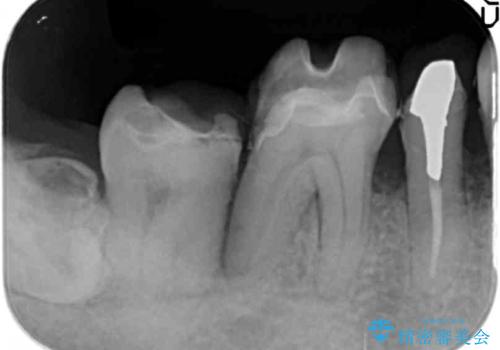

- 歯周病が進行し、根尖付近まで歯槽骨(歯を支える骨)の吸収が見られる歯の治療を希望され来院されました。

長期的な予後の見込めない奥歯の抜去を行い、骨と歯ぐきの治癒を待ち、インプラント治療を計画します。

インプラント周囲には骨の増生を埋入時に同時に行っています。